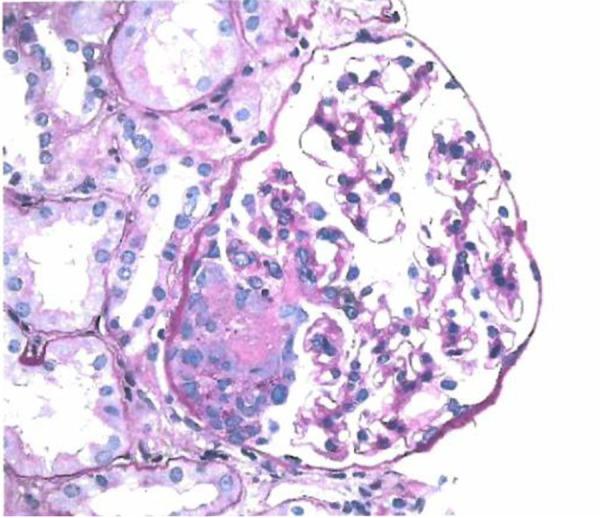

BACKGROUND Drug-induced anti-neutrophil cytoplasmic antibody (ANCA)-associated vasculitis (AAV) should be suspected in patients on certain medications who present with inflammatory ocular, constitutional, pulmonary, and/or renal manifestations. Here, we present a case of propylthiouracil (PTU)-induced AAV presenting initially with red eye, and review important diagnostic and management considerations for this uncommon disorder. CASE REPORT A 34-year-old woman with hyperthyroidism taking PTU presented with red eye, later followed by fevers and hemoptysis. She was found to have episcleritis, diffuse alveolar hemorrhage, and microhematuria. The infectious diseases workup was unrevealing. Laboratory evaluations were notable for a high-titer perinuclear ANCA and elevated anti-myeloperoxidase antibodies. Renal function was normal. She was ultimately diagnosed with PTU-induced AAV. PTU was promptly discontinued and she was treated with pulse-dose methylprednisolone for 3 days, followed by prednisone 60 mg daily. A kidney biopsy revealed pauci-immune focal segmental necrotizing and crescentic glomerulonephritis. Given an allergy to methimazole, she underwent thyroidectomy and was ultimately treated with rituximab. Her steroid doses are progressively being tapered and she has complete resolution of symptoms. CONCLUSIONS PTU-induced AAV is a rare and serious condition. Our patient presented with ocular symptoms prior to more commonly recognized pulmonary and renal manifestations. Patients may have favorable outcomes if PTU is discontinued promptly, but patients with vital-organ involvement may require treatment with steroids and may need additional immunosuppression.

一名 34 岁患有甲状腺功能亢进症的女性正在服用 PTU,出现眼红,随后出现发热和咯血。她被发现患有巩膜炎、弥漫性肺泡出血和镜下血尿。传染病检查无异常。实验室评估的特点是核周型 ANCA 滴度高和抗髓过氧化物酶抗体升高。肾功能正常。她最终被诊断为 PTU 诱导的 AAV。立即停用 PTU,并给予 3 天脉冲剂量甲基强的松龙,随后每天给予泼尼松 60mg。肾活检显示为少免疫性局灶性节段坏死性和新月体肾小球肾炎。由于对甲巯咪唑过敏,她接受了甲状腺切除术,最终接受了利妥昔单抗治疗。她的类固醇剂量逐渐减少,症状完全缓解。